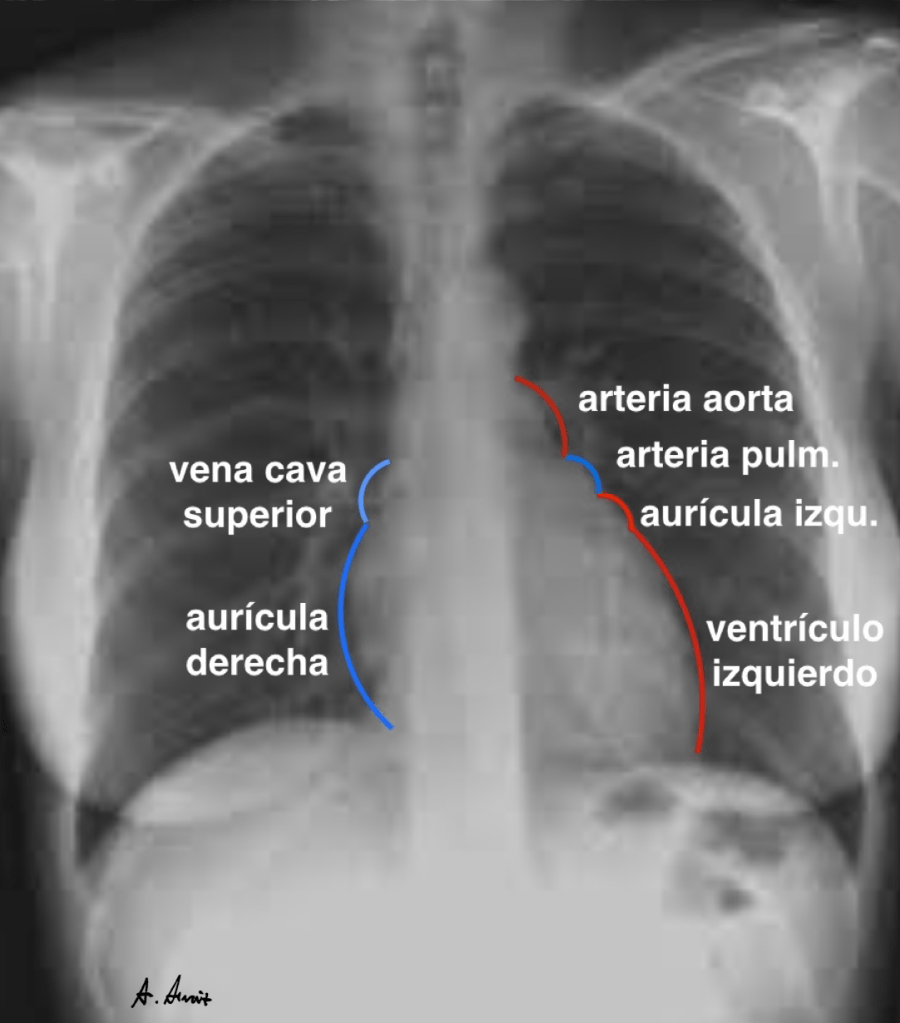

The following figures were made between 2014 and 2015. The simple shapes and bright colors reveal a somewhat naïve stage of drawing.